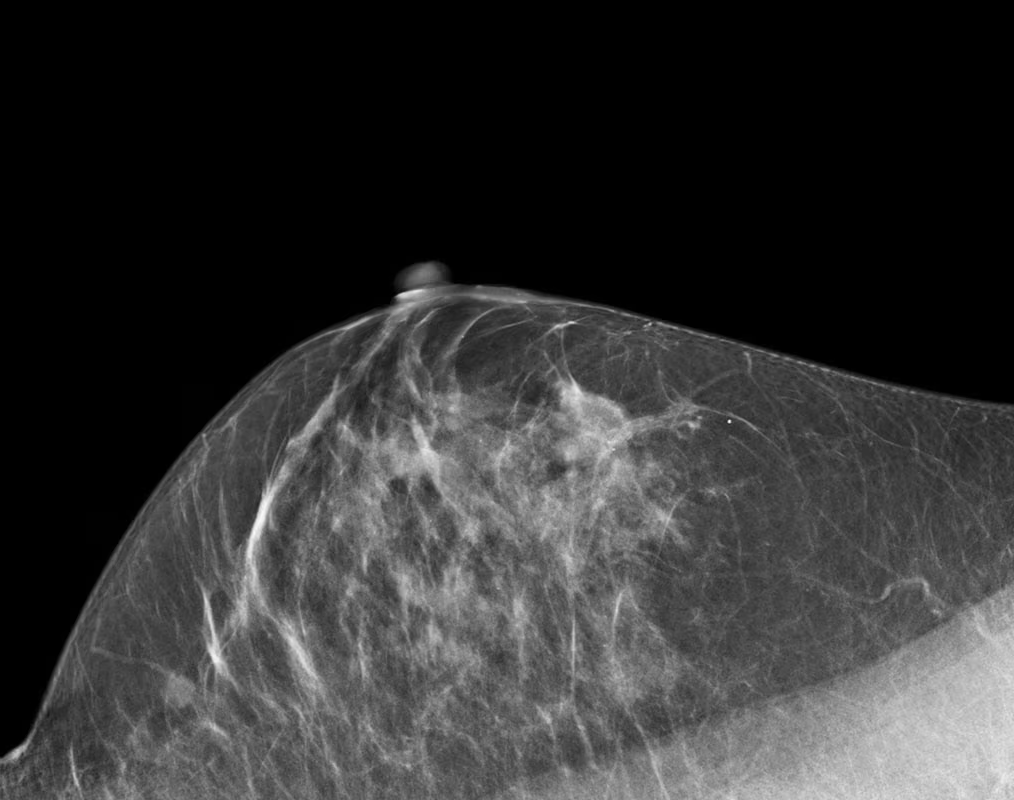

Si tratta di una metodica innovativa avanzata in grado di fornire informazioni aggiuntive rispetto alla mammografia digitale standard e alla tomosintesi. Consiste consiste nell’eseguire una semplice mammografia previa infusione di mezzo di contrasto iodato, che permette di unire i principi della mammografia digitale stessa con quelli della utilizzati dalla Risonanza magnetica, con cui condivide un’elevata sensibilità e specificità. L’impiego del mezzo di contrasto è utile per determinare le dimensioni di una lesione tumorale o per identificare alcuni tipi in particolare, oppure, ancora, nello studio prima o dopo un trattamento chemioterapico per la valutazione di un eventuale residuo di malattia.

E’ una procedura indolore e di semplice e rapida esecuzione che si propone come valida alternativa alla Risonanza magnetica della mammella, rispetto alla quale mostra i vantaggi di essere più rapida, meglio tollerata dalle pazienti ed anche molto meno costosa.